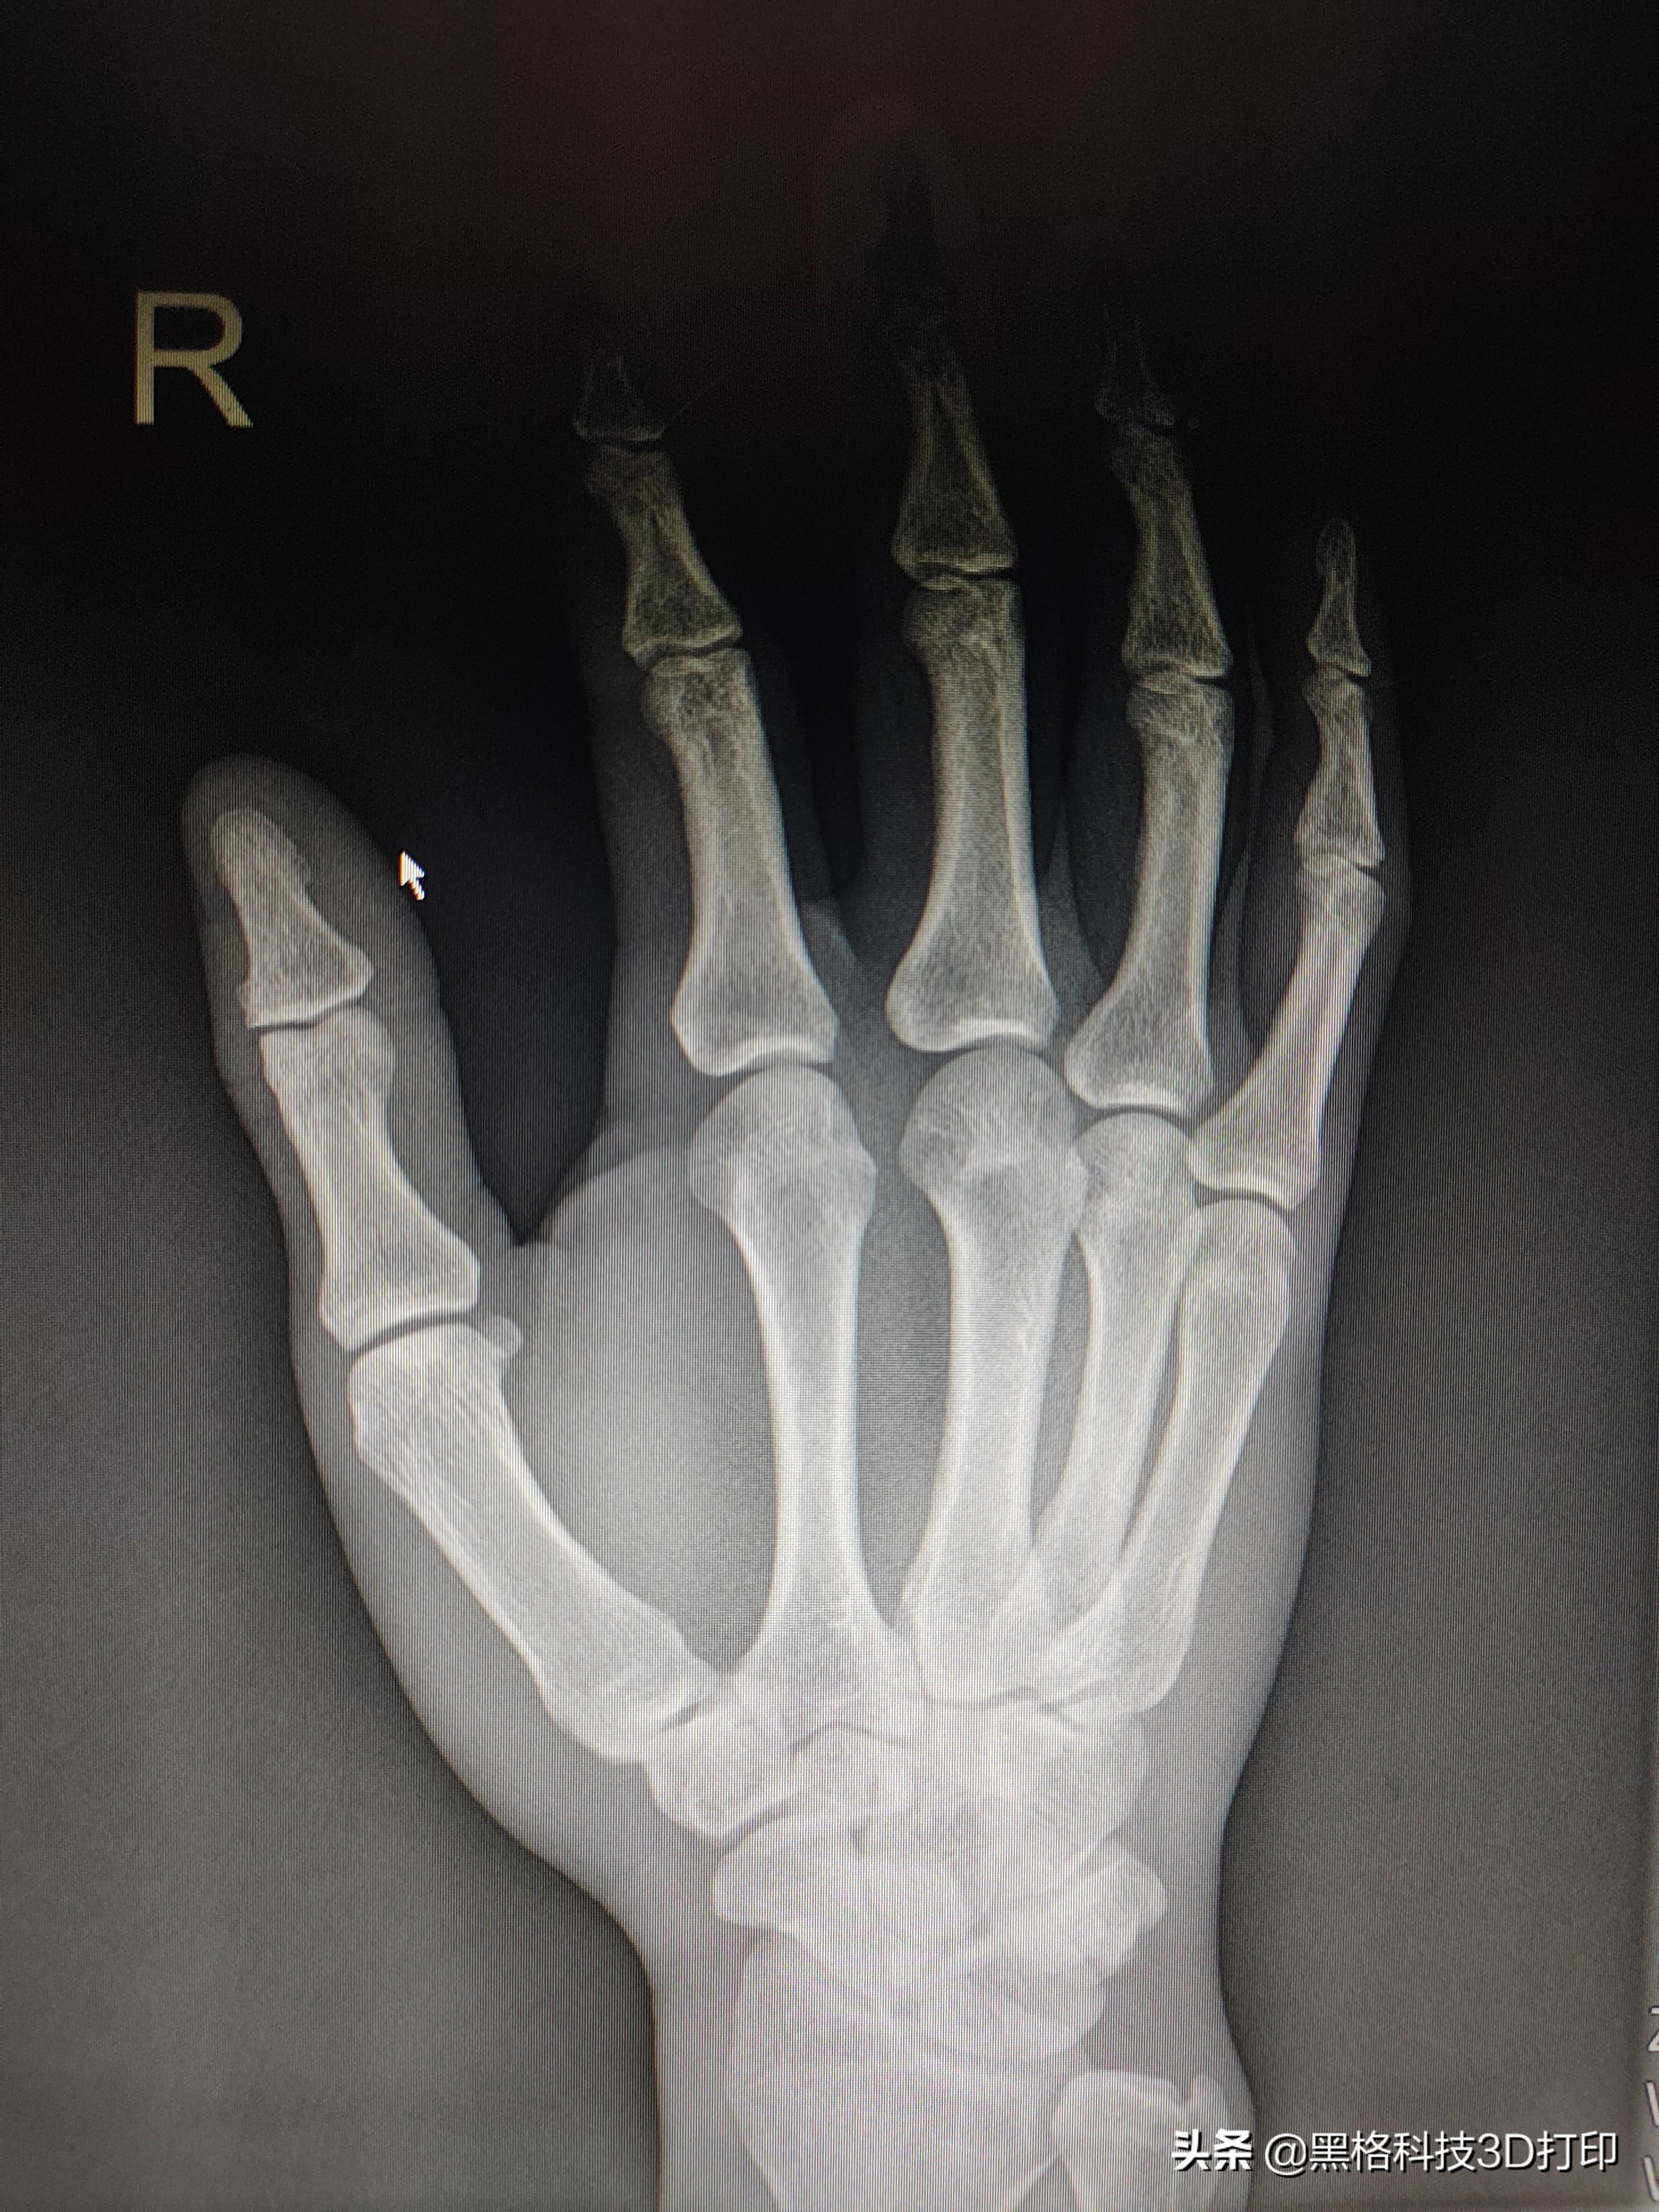

一次搬运过程中,货物突然从高处跌落,为了不让员工受伤,付先生及时接住了货物,结果导致 右手第5掌骨骨折。

因患处无明显移位,医生便直接使用热塑板进行了固定,限制手掌活动以便恢复。

医生根据付先生的需求,为他推荐了欣适康。黑格科技通过扫描付先生的手掌,为他 打印了一款掌骨固定器 ,能够稳定第五掌骨的骨头。

而且佩戴着欣适康也能直接进行X光扫描检查,无需脱下。

付先生换上通过扫描他本人手掌定制出的手掌掌骨固定支具后,日常生活立刻变得方便和轻松多了,不仅不再需要担心热塑板是否会松脱滑落,而且在炎热的天气里摆脱了纱布和魔术贴的束缚,也能更舒适地进行商务活动。